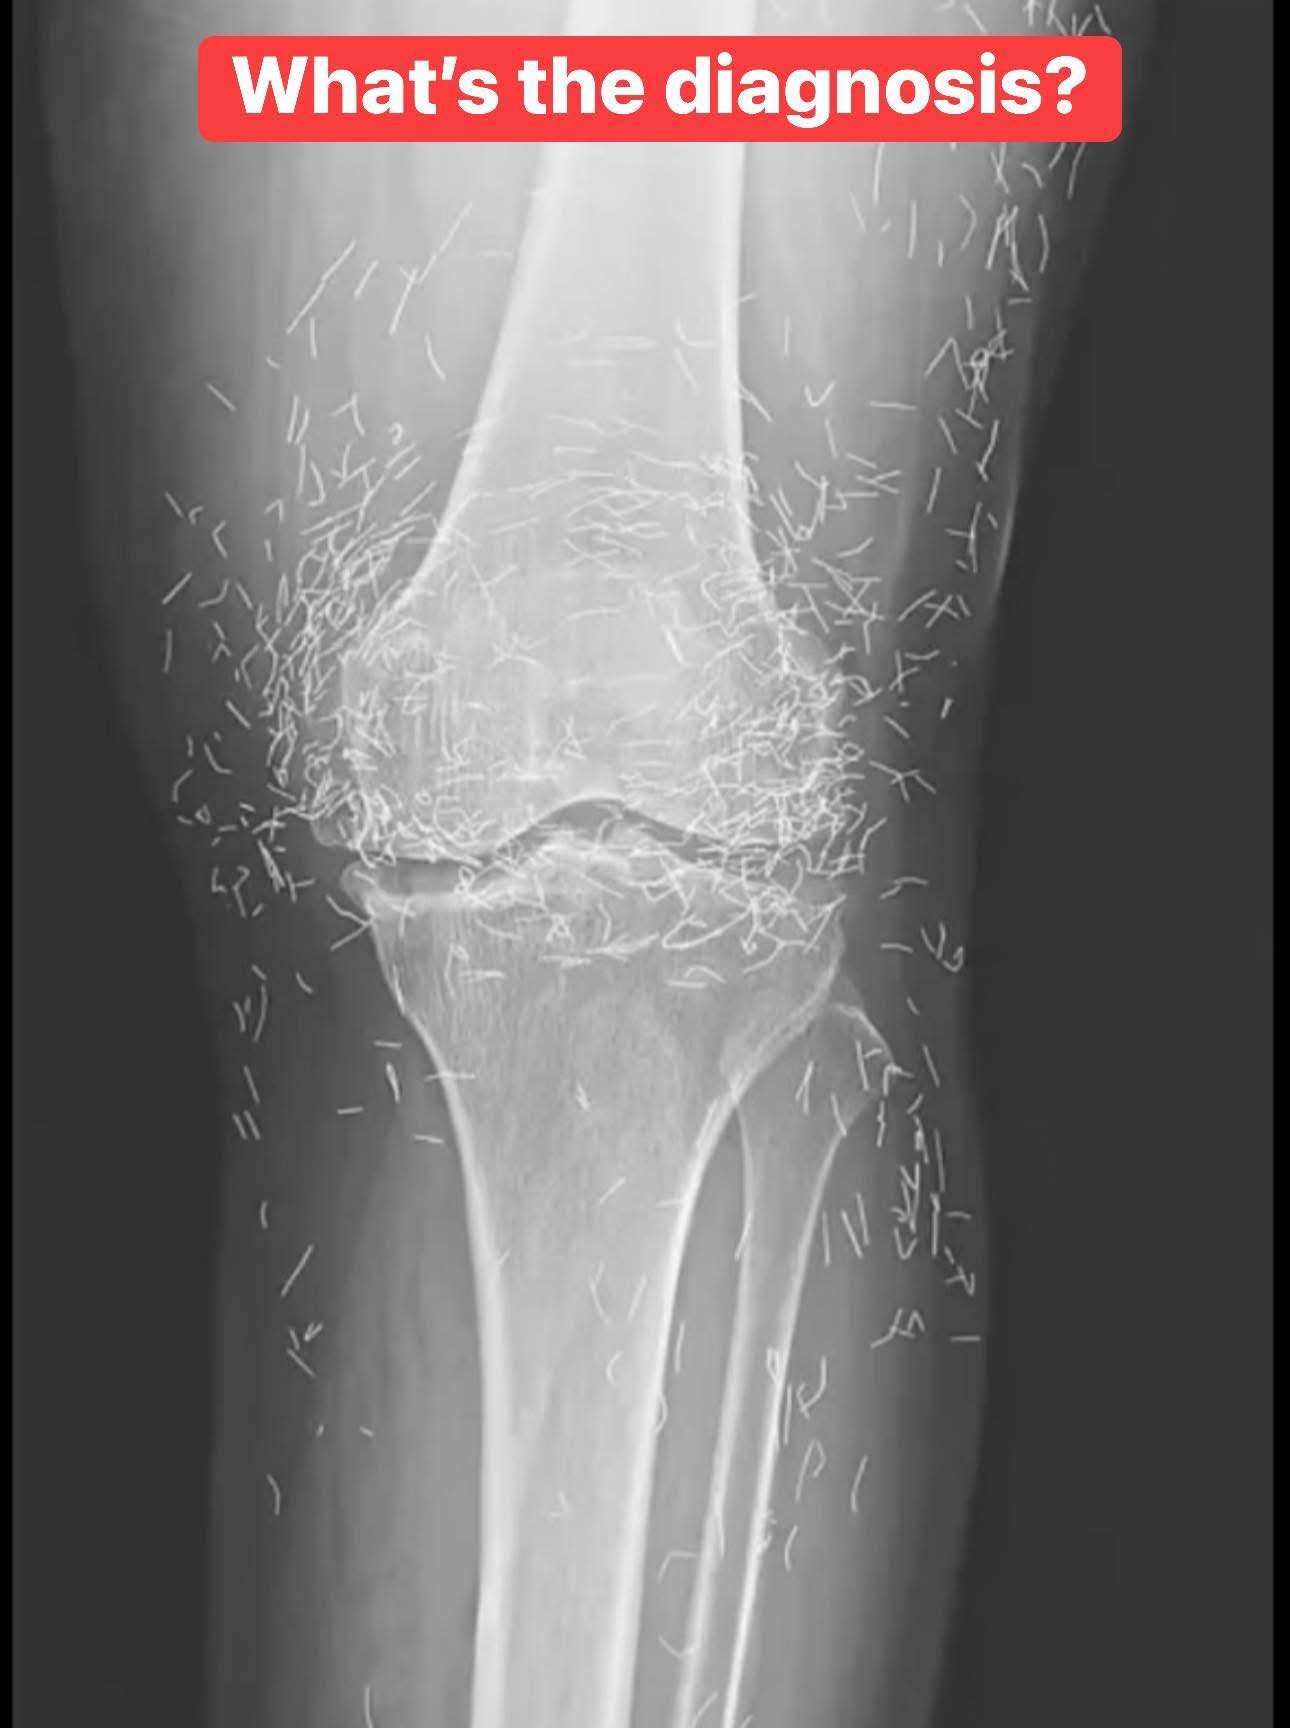

A 65-Year-Old Woman with Chronic Knee Pain: What Could Be the Diagnosis?

Chronic knee pain is a common complaint among older adults, and it can have many causes, ranging from simple overuse to more complex underlying conditions. When a 65-year-old woman comes into a clinic after months of struggling with knee pain that doesn’t improve despite trying various treatments—including traditional Chinese medicine—it’s time for a deeper look.

In her case, after trying multiple treatments without success, the decision was made to take an X-ray during her visit. Based on this clinical scenario, let’s explore the most likely causes of her knee pain and the potential diagnosis.

An X-ray would typically show joint space narrowing, bone spurs (osteophytes), and subchondral sclerosis (increased bone density underneath the cartilage).

The X-ray – A Key Diagnostic Tool

X-rays are typically the first imaging tool used to evaluate chronic knee pain. They allow doctors to see structural issues in the bones, joint spaces, and alignment of the knee. Based on the findings from the X-ray, we can narrow down potential diagnoses.

1. Osteoarthritis: The X-ray may reveal joint space narrowing, osteophytes (bone spurs), and subchondral sclerosis. These are signs of cartilage loss and bone changes associated with OA.

Given the patient’s age and the fact that her knee pain has been chronic and resistant to multiple treatments, osteoarthritis (OA) is the most likely diagnosis. The X-ray would likely show signs of cartilage breakdown, joint space narrowing, and possibly osteophytes (bone spurs) in the knee joint.

While other conditions like rheumatoid arthritis, patellofemoral pain syndrome, or meniscus tears could also be possible, OA is the most common cause of chronic knee pain in older adults, especially when it resists treatment.